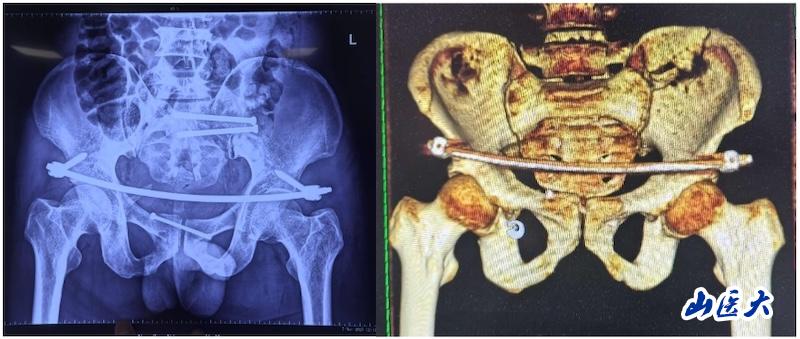

該患者在駕駛三輪車時發生車禍,導致骨盆骨折,經過當地醫院對癥治療后轉入我校第二醫院急診科。由于血色素持續下降,血管外科首先進行了血管介入栓塞處理,隨后轉入骨科創傷病區,由孫海鈺團隊接續治療。經過詳細檢查和評估,孫海鈺主任、賀冬冬副主任醫師、王歡副主任醫師為患者制定了運用UCRT解鎖復位技術,結合天璣機器人及O-arm術中影像系統為其實施骨盆閉合復位的手術治療方案。3月6日,孫海鈺團隊在骨科老一輩專家尹蕓生主任的指導及麻醉師、技師、器械護士和巡回護士的通力協助下,成功運用微創新技術為患者實施了手術。

據孫海鈺介紹,骨盆髖臼骨折是一種嚴重的創傷,傳統開放復位內固定術創傷大、恢復慢,而閉合復位則具有微創、出血少、恢復快等優點。隨著醫療技術的不斷進步,UCRT解鎖復位技術結合天璣機器人及O-arm術中影像系統為骨盆骨折治療提供了更加精準、微創的解決方案,該技術代表了當前骨盆骨折治療的前沿方向。